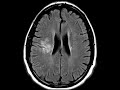

Developmental Venous Anomaly

These images show a prominent enhancing vascular structure with surrounding T2 FLAIR hyperintensity in the posterior right frontal lobe with smaller vessels draining into it from the deep white matter and subsequently draining to cortical veins. This appearance represents the caput medusae or head of medusa sign that is characteristic of a developmental venous anomaly (DVA). These are the most common vascular malformations of the brain, are usually found incidentally, and can be associated with cavernomas. The frontoparietal location is the most common site. It is important to identify in preoperative cases as cautery may lead to venous infarction. Multiple DVAs can be seen with Blue Rubber Bleb Nevus Syndrome.The surrounding T2 FLAIR abnormality seen in this case may represent gliosis or edema related to chronic venous insufficiency in this region.